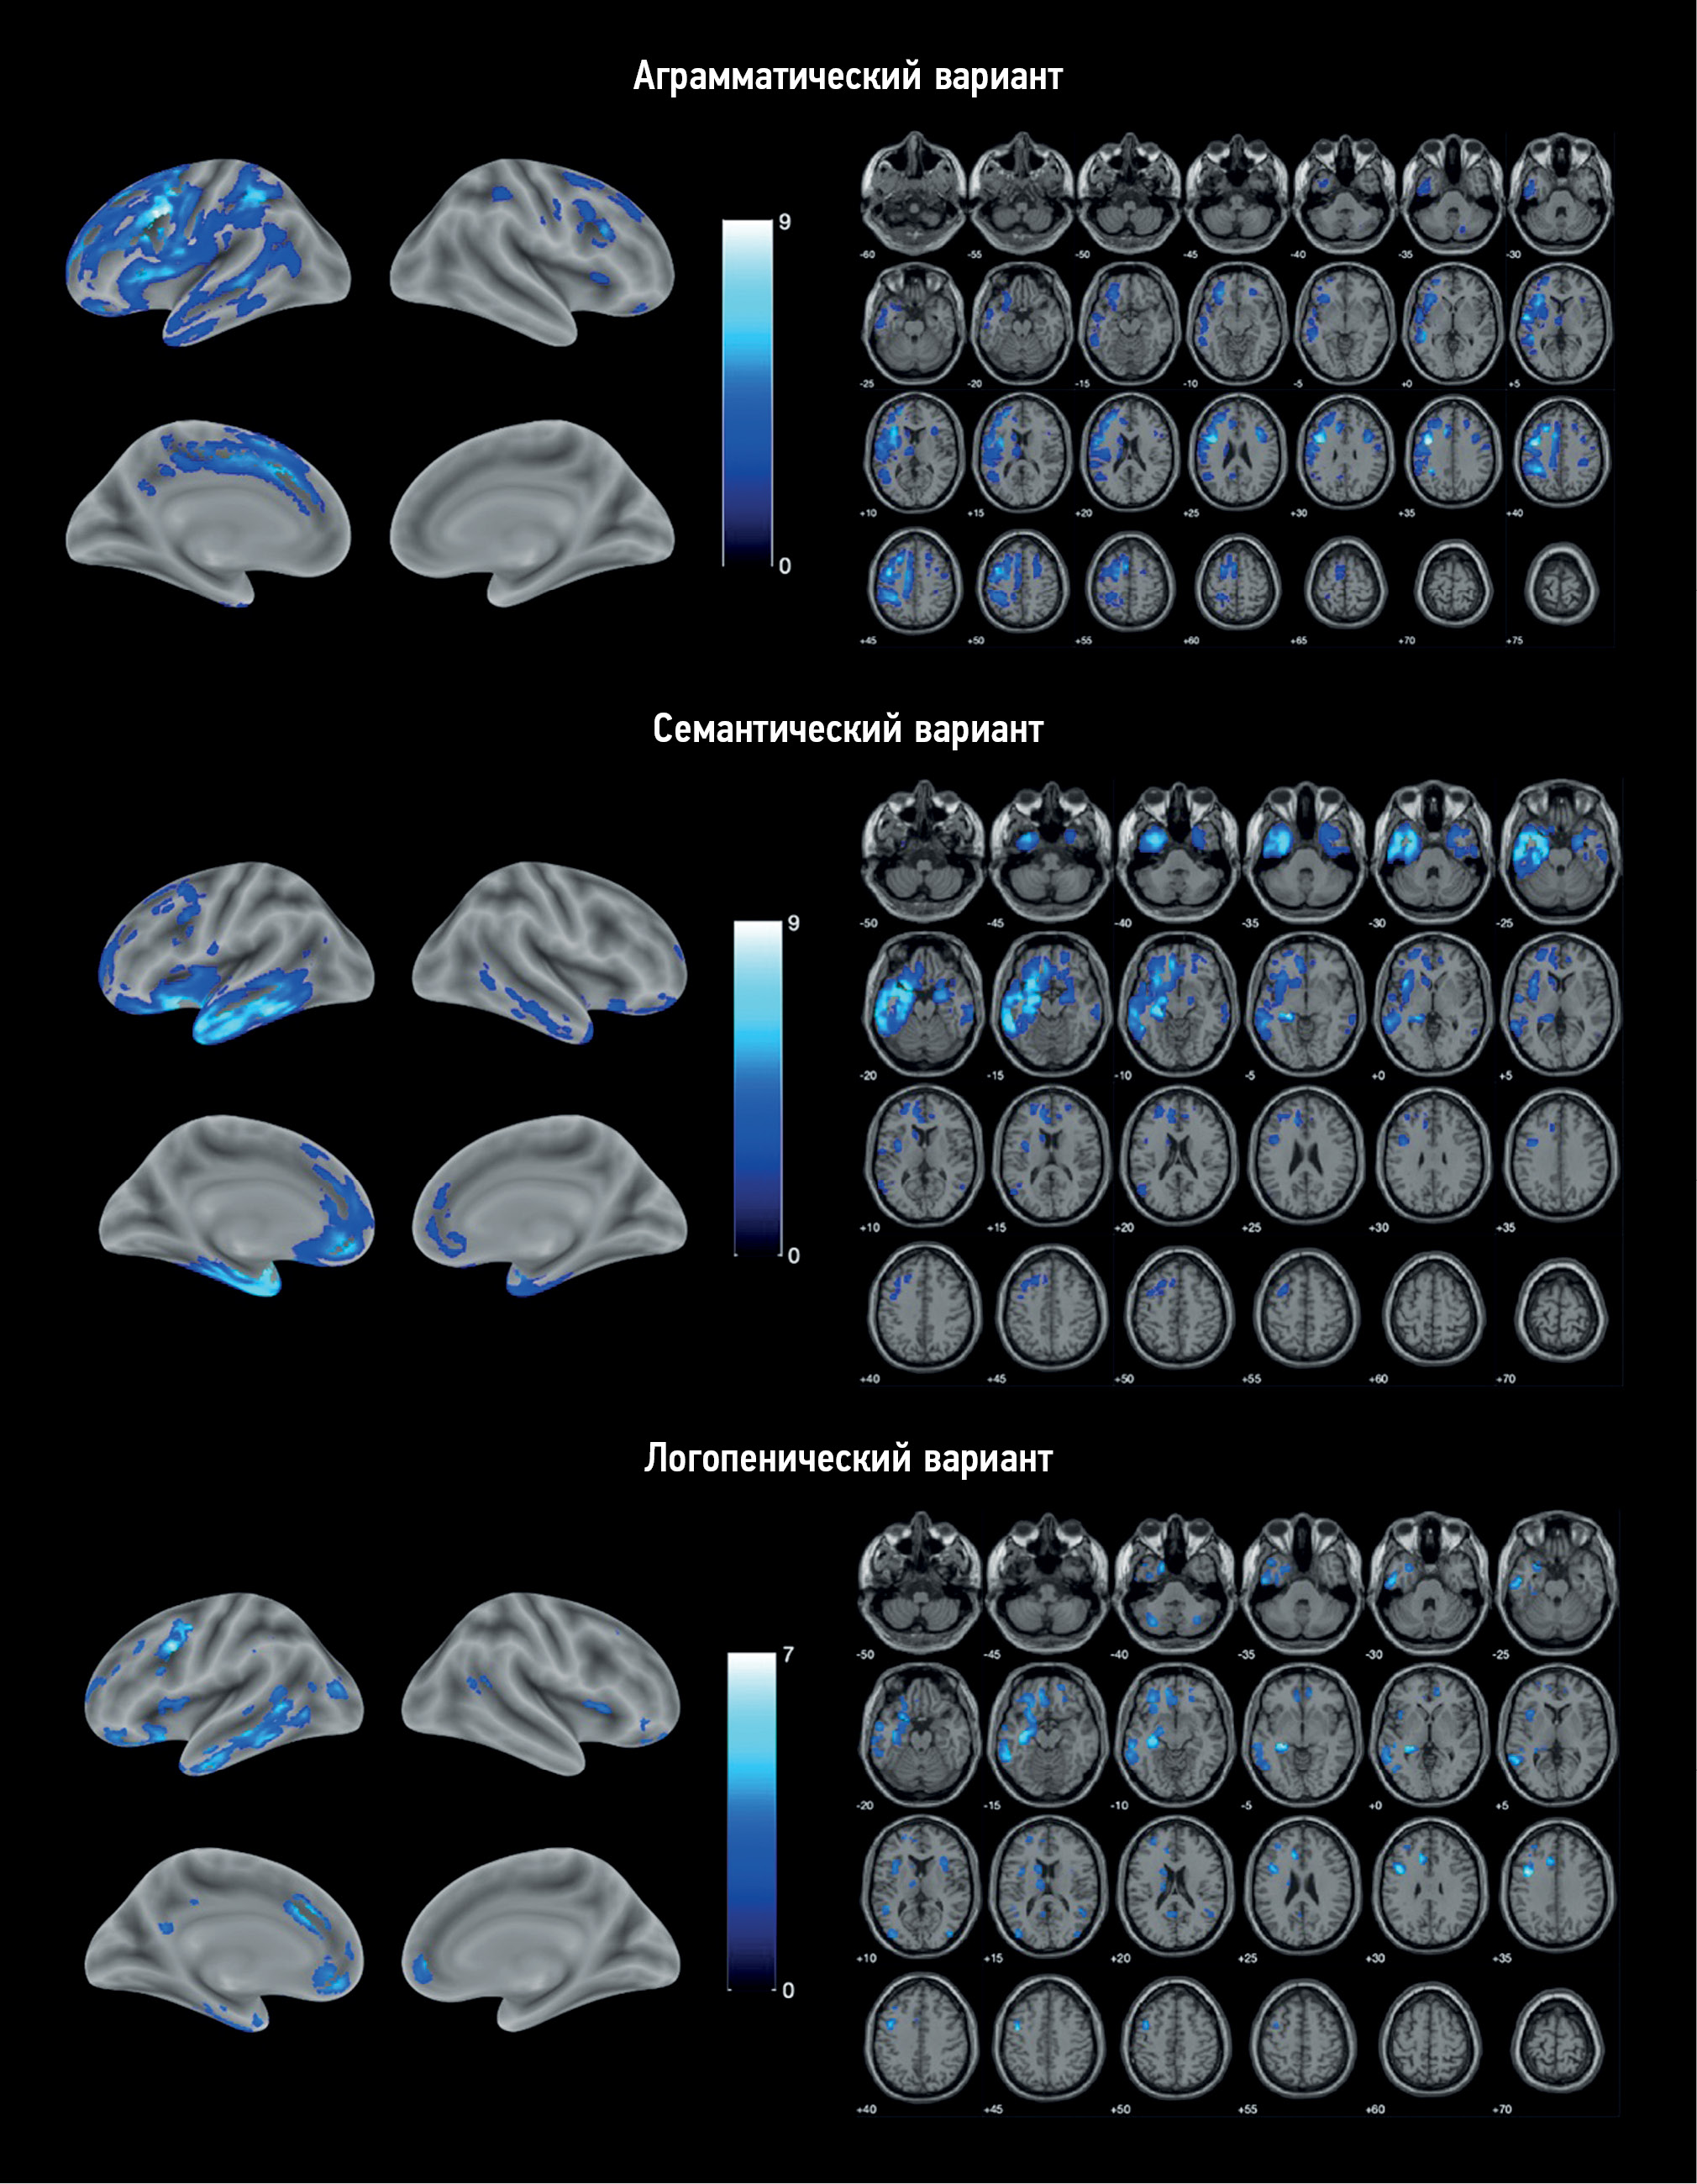

RESULTS: The study enrolled 25 patients with nonfluent, 11 with semantic, and 9 with logopenic variants of primary progressive aphasia, as well as 20 healthy volunteers. Voxel-based morphometry showed a specific atrophy pattern in each of the variants of primary progressive aphasia, with predominant involvement of the frontal and insular lobes in nonfluent, temporal lobe and hippocampus in semantic, and a more diffuse frontotemporal pattern in logopenic variants.

CONCLUSIONS: The study revealed gray matter atrophy patterns specific to each variant of primary progressive aphasia. The obtained results mainly correspond to the clinical presentations of the disease. Moreover, some findings (e.g., absence of the posterior perisylvian atrophy and reduced motor cortex volume in the logopenic variant, atrophy of the orbitofrontal cortex and cerebellum in the nonfluent variant, and premotor cortex, precentral, and inferior frontal gyrus degeneration in the semantic variant) do not correlate with the usual understanding of primary progressive aphasia pathogenesis and require further study.